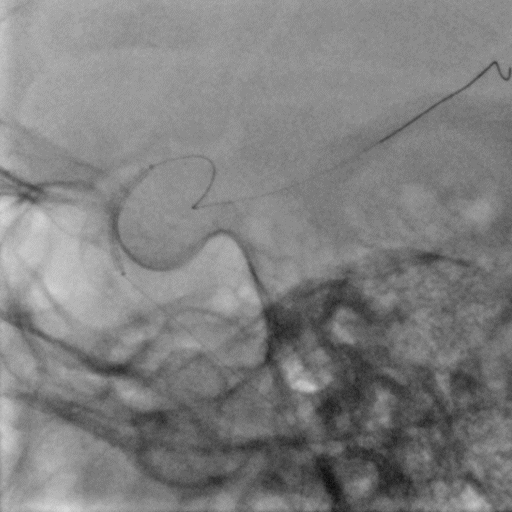

左侧颈总动脉正侧位造影

常规消毒、铺巾后,采用改良Seldinger技术穿刺右桡动脉。

造影导丝和Sim2造影导管将7F EasyRadial™输送导管置于颈内动脉:

路径图下,微导丝越过颈内开口狭窄段达岩骨段,取2.5*15mm 颅内球囊扩张导管送至左侧颈内动脉开口狭窄处给予预球囊扩张成形术。

球囊扩张后狭窄改善。

输送保护伞至颈内动脉C1末端平直段。

撤微导丝。

沿保护伞导丝送入7.0*50mm Wallstent颈动脉支架至颈内动脉开口处。

准确定位后释放支架。

支架释放后造影显示残余狭窄40%。

再次沿保护伞导丝送入4.0*25mm 颅内球囊扩张导管,越过支架送至颈内动脉开口狭窄最严重处给予球囊后扩张成形术。

术后造影显示支架内无明显残余狭窄,颅内血管无明显栓塞。